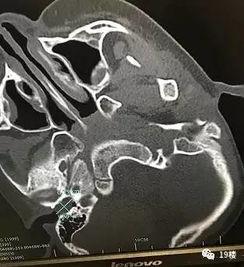

你知道吗?耳屎其实是一种叫做“耵聍”的物质,它是我们耳朵的一种自我保护机制。耵聍可以防止耳朵受到外界的伤害,同时还能吸附灰尘和细菌,保持耳朵的清洁。但是,如果耳屎过多,就会堵塞耳道,影响听力,甚至引发炎症。

三、严重耳屎视频引发的思考